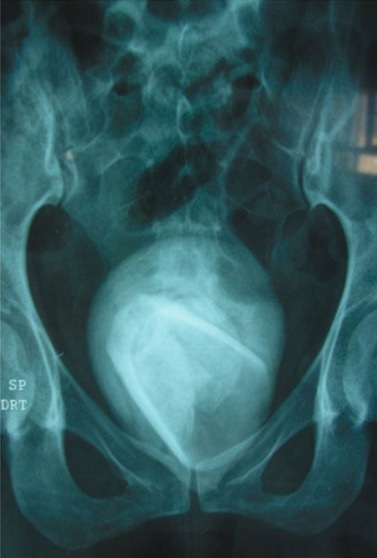

A 45-year-old woman went to the hospital with a mild urinary tract infection (UTI), but it turned out she had a tumbler lodged in her bladder.

The scan result revealed she had an 8cm-wide bladder stone inside her.

Her urine had shown a red blood cell range of 23-25, when the normal human will only show four or less, a report states.

The object was removed via open surgery, and she was discharged two days later. She is now thought to be fully recovered

Doctors who treated with the strange case in Tunisia believe it was implanted during sexual assault, but they have not offered any proof from the patient to back up their assertion.